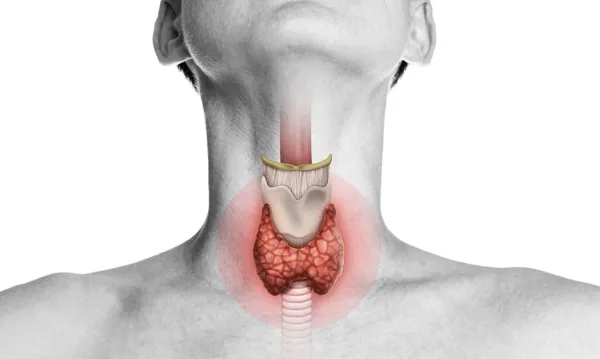

علامات تشير إلى اختلال عمل الغدة الدرقيةكيف تختار البعوضة إنسانا دون آخر؟ السر في الرائحةسر استمرار العلاقة الزوجية: 8 طرق فعّالة لتعزيز الحب والألفةحالة الطقس في فلسطين يوم الثلاثاءعالمة تحدد مرحلة عمرية حرجة تبدأ فيها العظام بفقدان صلابتهاروني ينتقد تصرف لاعبي ليفربول مع صلاح: احترموا زملائكمغروسي: أي اتفاق بين واشنطن وطهران دون الوكالة "وهم""نتائج 7 أكتوبر , لا إسرائيل".. ترامب يعلن سبب حرب إيران5 مؤشرات حيوية تكشف سر الشيخوخة الصحية قبل ظهور المرض بعقوددراسة: طول فترة الخصوبة تؤثر على تدهور الذاكرة لدى النساءعلامات تشير إلى اختلال عمل الغدة الدرقيةكيف تختار البعوضة إنسانا دون آخر؟ السر في الرائحةسر استمرار العلاقة الزوجية: 8 طرق فعّالة لتعزيز الحب والألفةحالة الطقس في فلسطين يوم الثلاثاءعالمة تحدد مرحلة عمرية حرجة تبدأ فيها العظام بفقدان صلابتهاروني ينتقد تصرف لاعبي ليفربول مع صلاح: احترموا زملائكمغروسي: أي اتفاق بين واشنطن وطهران دون الوكالة "وهم""نتائج 7 أكتوبر , لا إسرائيل".. ترامب يعلن سبب حرب إيران5 مؤشرات حيوية تكشف سر الشيخوخة الصحية قبل ظهور المرض بعقوددراسة: طول فترة الخصوبة تؤثر على تدهور الذاكرة لدى النساء